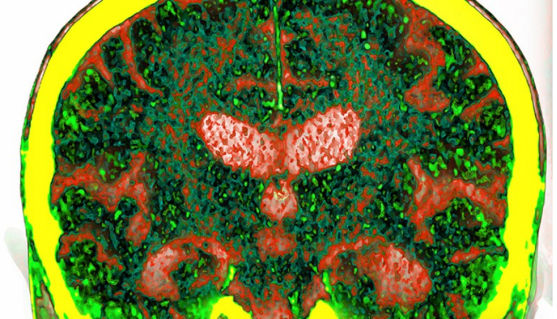

Using blood samples from more than 50,000 adults in the UK Biobank, researchers discovered four proteins closely related to dementia: GFAP, NEFL, GDF15 and LTBP2, as shown in the figure: